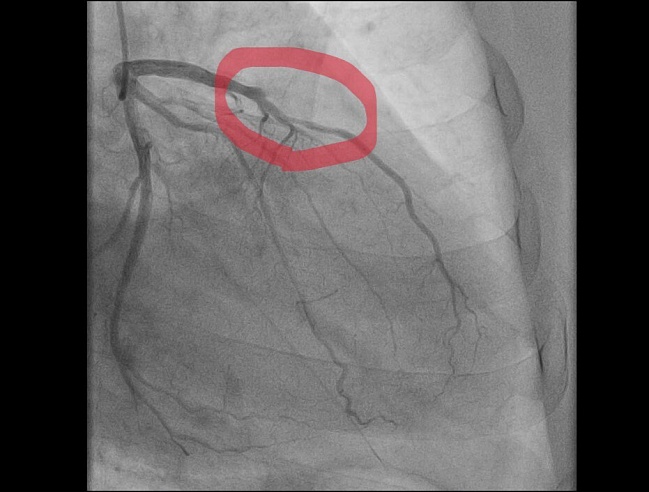

Недавний клинический случай балаковских медиков - яркий пример коварности сочетания физнагрузки и мороза: 59-летний мужчина почувствовал острую боль в груди во время уборки снега. Бригада "скорой" диагностировала "острый инфаркт миокарда" и немедленно начала лечение. Пациента доставили в сосудистый центр, где выявили тромботическую окклюзию передней межжелудочковой артерии* — сосуда, который в медицинской среде называют "артерией вдов" из-за высокого риска летального исхода при ее поражении. Операционная бригада балаковских медиков провела экстренное стентирование, полностью восстановив проходимость артерии.